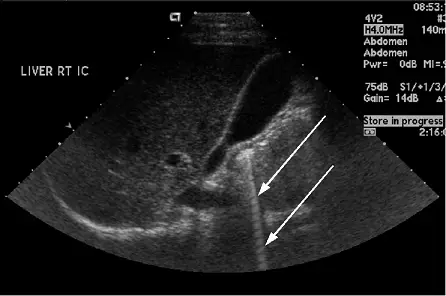

下圖中箭號所指的區域代表: 圖片

圖片為腹部超音波影像(LIVER RT IC,右肝肋間切面,4V2 探頭、4.0 MHz)。影像左側可見正常肝臟實質回音,中央偏右方有兩個白色箭頭,指向一個自淺部延伸至深部的**亮白色條帶狀(bright streak)**結構,呈現連續的高亮度直線延伸,並不隨深度衰減、且無離散的平行等距線條,整體呈現一種向深部延伸的「光束(searchlight)」外觀。

此影像特徵符合**餘音假影(ring-down artifact)**的典型表現:

• 起源自高反射介面(如氣泡或被液體包圍的氣體)

• 向深部延伸的連續高亮度條帶

• 不同於慧尾假影(comet-tail artifact)的逐漸衰減三角形狀

• 常見於腹腔氣體、膽囊積氣或膽道積氣(pneumobilia)等狀況